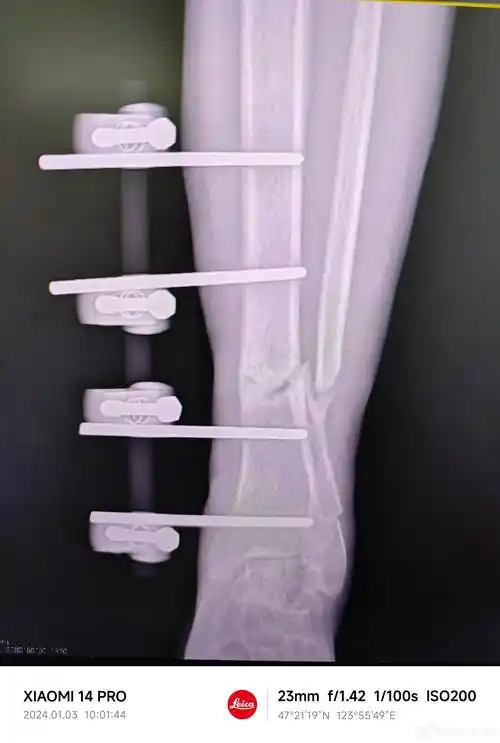

胫腓骨远端骨折外固定架